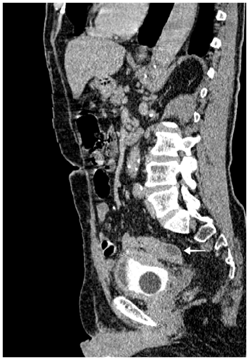

An antibiotherapy was started and retrograde and urinary uretro-cystography was performed. Retrograde cystography showed diverticular bladder with opacification of the sigmoid colon up to the half of the transverse colon (Figure 1) (Figure 2).

Figure 1 Frontal view of retrograde urethrocystography showing opacification of the sigmoid and descending colon.

Figure 2 Profile view of retrograde urethrocystography showing opacification of colon until half of his transverse portion.

Usually, Because of high pressure in the intestine, the fistula works from the intestine to the bladder except when there is an obstacle on the lower urinary tract, as was the case of our patient resulting in opacification of the intestine during cystography thus permitting diagnosis of entro-vesical fistula.